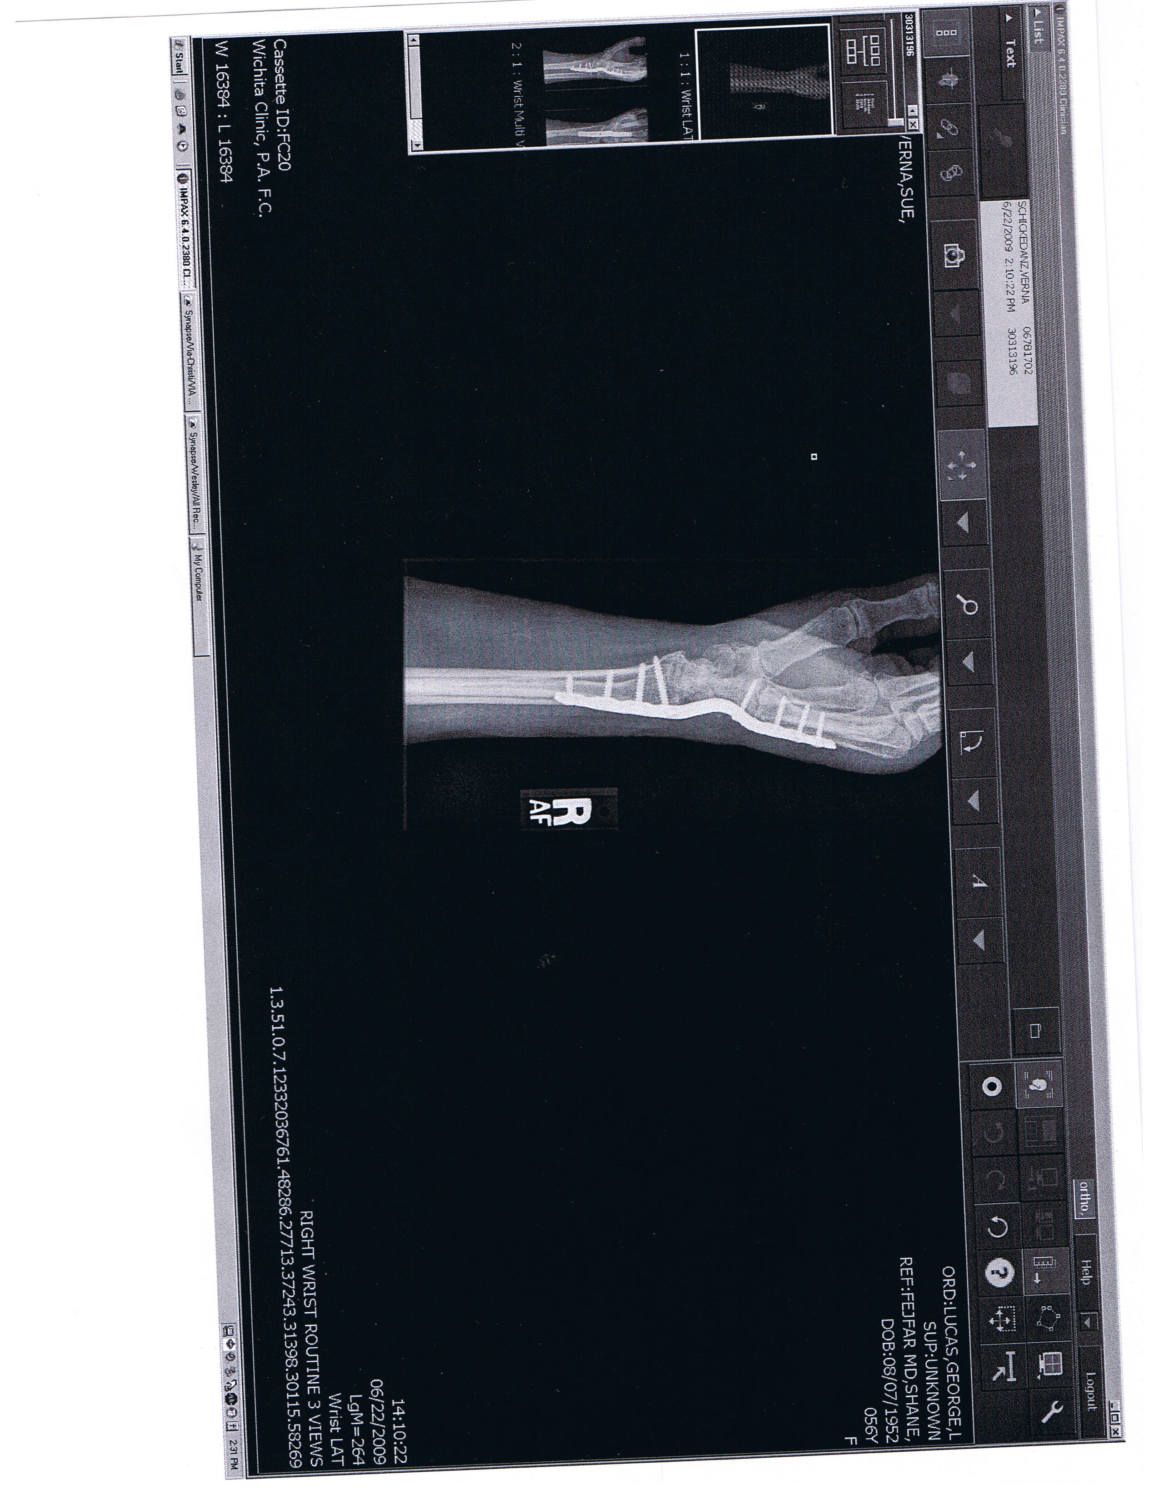

Checoukan they did exrays on my hand of course that was just to make sure I hadn't broken any bones. Tendons are pretty tender things to deal with. My original injury tore all the tendons across my wrist leaving me unable to use my fingers at all. They had to cut them off and pull them up and reattach them to my knuckles. My thumb was then pinned into my wrist and another pin was placed to hold the left side of my wrist secure. But then years of redamaging it and arthritis it finally became necessary to put the plates and screws in and fuse the rest of the wrist. Here is a picture of a scan of an exray done on my hand and wrist. Click to enlarge

Anyway, stretching a tendon causes a lot of pain and it takes a long time to heal. It's kind of like stretching a rubber bunge cord beyond it's limits. They don't give easy and it's harder to get them to go back to their original shape. I just have to live with the pain I guess. It does bother me it is getting worse but it's probably my own stupidity for refusing the splint.